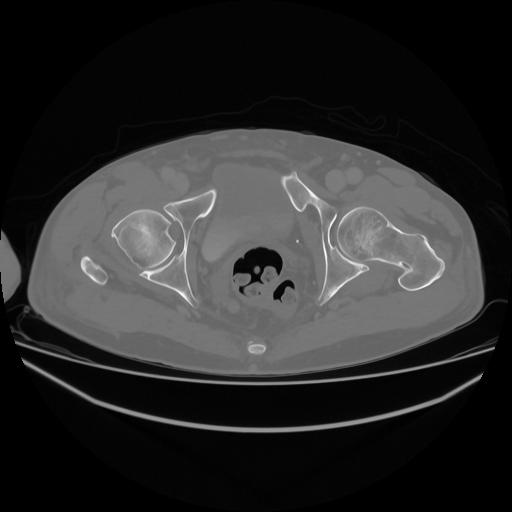

5 CUERPO,CE,Vol,1.0,CUERPO,,